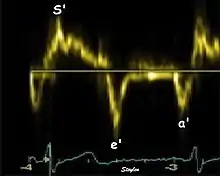

As the ventricle relaxes, the annulus moves towards the base of the heart, signifying the volume expansion of the ventricle. The peak mitral annular velocity during early filling, e' is a measure of left ventricular diastolic function, and has been shown to be relatively independent of left ventricular filling pressure.[12][13][14] If there is impaired relaxation (Diastolic dysfunction), the e' velocity decreases. After the early relaxation, the ventricular myocardium is passive, the late velocity peak a' is a function of atrial contraction. The ratio between e' and a' is also a measure of diastolic function, in addition to the absolute values.

Annular velocities summarize the longitudinal contraction of the ventricle during systole, and elongation during diastole. Peak velocities are commonly used.

Systolic function

Peak systolic annular velocity (S') of the left ventricle is as close to a contractility measure as you can get by imaging[4] (bearing in mind that any imaging method only measures the result of fibre shortening, without measuring myocyte tension). S' has become a reliable measure of global function[5][6][7][8] It shares the advantage of annular displacement, that it is reduced also in hypertrophic hearts with small ventricles and normal ejection fraction (HFNEF), which is often seen in Hypertensive heart disease, Hypertrophic cardiomyopathy and Aortic stenosis.[9]